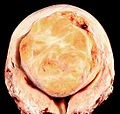

A relatively large submucosal leiomyoma; it fills out the major part of the endometrial cavity |